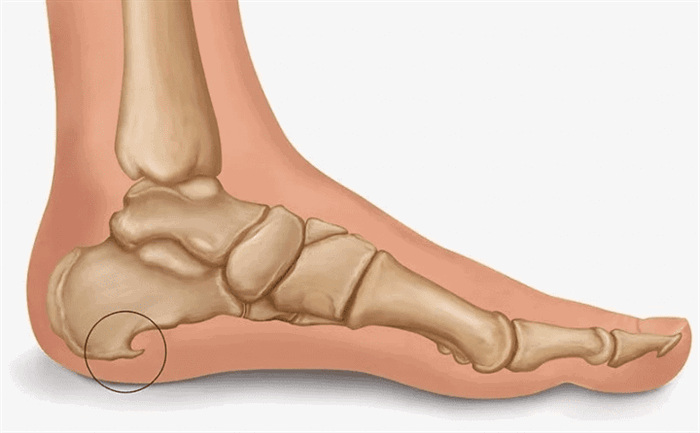

Пяточная шпора

Пяточная шпора – это костный нарост в области подошвенной поверхности пяточной кости. Его появление связано с постоянным раздражением места прикрепления к пяточной кости подошвенного апоневроза. Это раздражение обычно возникает при усиленных физических нагрузках на стопу.

Воспаление начинает захватывать расположенные рядом ткани, в частности, кость и сухожилия. На поверхности костной ткани начинается отложение солей кальция и рост отростка (остеофита), который и носит название пяточной шпоры. Он еще больше повреждает фасцию, и патологический круг замыкается. Без помощи врача ходьба становится невыносимо болезненной.

- подошвенная (внутренняя) пяточная шпора: наиболее распространенный вариант, при котором остеофит располагается в нижней части пяточной кости;

- ахиллова (задняя, верхняя) пяточная шпора: отросток формируется в месте прикрепления ахиллова сухожилия; эта разновидность патологии встречается крайне редко.

Пяточная шпора представляет собой депозит кальция на нижней части пяточной кости. На рентгеновском снимке, пяточная шпора может выступать вперед на 0.5-1 см. Хотя пяточные шпоры часто безболезненны, тем не менее, они могут быть причиной достаточно сильных болей. Пяточные шпоры часто ассоциированы с подошвенным фасцитом. Подошвенный фасцит является наиболее частой причиной болей в нижней части пятки. Приблизительно 2 миллиона пациентов в США лечатся по поводу подошвенного фасцита каждый год. Подошвенный фасцит возникает, когда сильная полоска ткани, которая поддерживает свод стопы (плантарная фасция), раздражается и воспаляется. Пяточные шпоры на задней части пятки нередко также ассоциированы с воспалением ахиллова сухожилия (тендинитом) и могут быть причиной болезненности и болей в задней части пятки, усиливающейся при разгибании стопы.